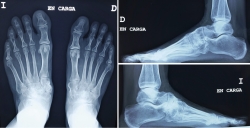

Se realizó estudio mediante tomografía computarizada (TC) (Figura 3) donde podemos ver la falta de fusión de la osteotomía de la primera cuña, los cambios degenerativos escafocuneanos, la fusión de la tercera cuña con el cuboides y el hundimiento de la columna medial a nivel transcuneano.

Figura 3. Imágenes de la tomografía computarizada.